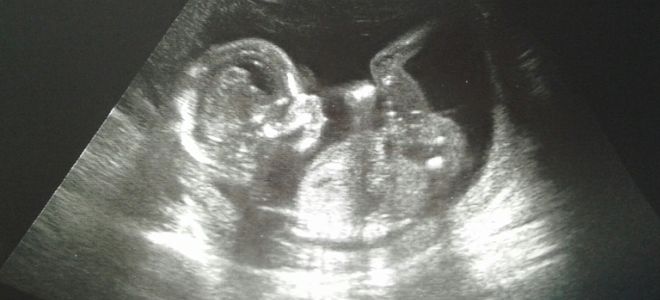

УЗИ на 16 неделе беременности – что смотрят?

Ультразвуковое исследование на 16-й неделе беременности выполняется исключительно по медицинским показаниям. Процедура назначается в случае, если у беременной есть жалобы или если результаты предыдущих обследований не соответствуют нормам.

Ключевые параметры, на которые обращают внимание специалисты во время УЗИ:

- частота сердечных сокращений плода;

- расположение внутренних органов и частей тела ребенка (размеры головы, окружность груди, живота и конечностей);

- положение плода;

- оценка предлежания плаценты;

- объем и качество амниотической жидкости.

Пол ребенка на 16 неделе беременности

Чаще всего на сроке 16 недель беременности ультразвуковое исследование не проводится, так как пол ребенка уже установлен, а развитие плода оценено. Тем не менее, если ранее не удалось провести данное обследование, врачи могут назначить его сейчас. В процессе УЗИ также обращают внимание на пол будущего малыша. Все зависит от того, как именно расположен ребенок в утробе: если он находится спиной к передней стенке живота матери, то увидеть его половые органы может быть затруднительно.